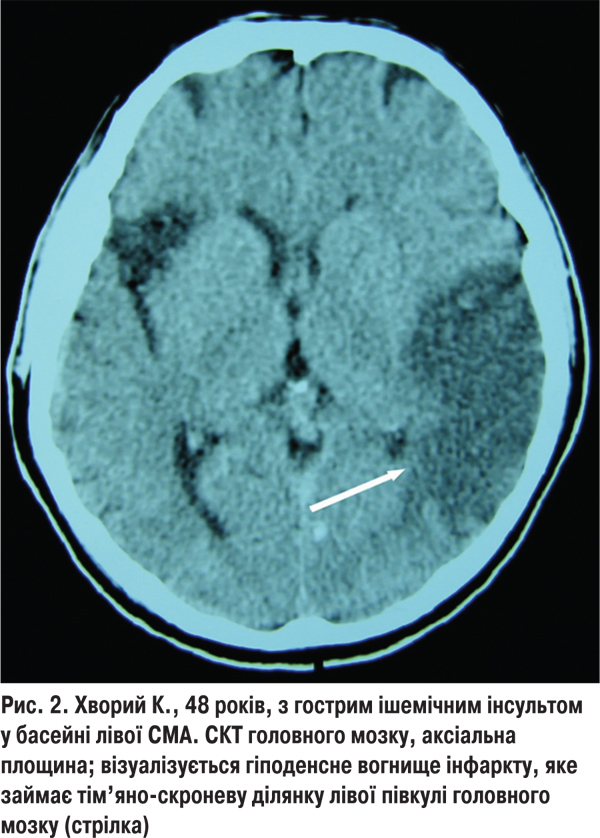

Із 113 обстежених з кардіоемболічним підтипом інфаркту мозку в 44 (29,9%) хворих 1-ї групи найчастішим джерелом емболії був атеросклеротичний або постінфарктний кардіосклероз із миготливою аритмією, що спричиняло ураження СМА на різних рівнях і зумовлювало відповідну клініку інфаркту мозку в кожному конкретному випадку. У 6 (4,1%) хворих виникав територіальний інфаркт, який був зумовлений оклюзією головного стовбура СМА (рис. 2). У такому разі спостерігався виражений початковий неврологічний дефіцит і повільні темпи відновлення втрачених неврологічних функцій. У 23 (15,6%) хворих ішемічне вогнище було зумовлене закупоркою глибоких гілок СМА і локалізувалось у підкірково-капсулярній ділянці півкулі головного мозку. У 15 (10,2%) хворих ураження кіркових гілок СМА або ПМА призводило до розвитку поверхневих кортикальних інфарктів, а клінічна картина характеризувалася швидким регресом осередкових неврологічних симптомів. Фоновий неврологічний дефіцит за шкалою NIHSS у хворих з кардіоемболічним підтипом ішемічного інсульту і сприятливими наслідками становив 11,6±2,6 бала, а на 21- шу добу — 6,5±1,3 бала. Після лікування 34 (77,2%) пацієнти не потребували сторонньої допомоги у виконанні найважливіших життєвих функцій, водночас 10 (22,8%) хворих залежали від сторонньої допомоги.